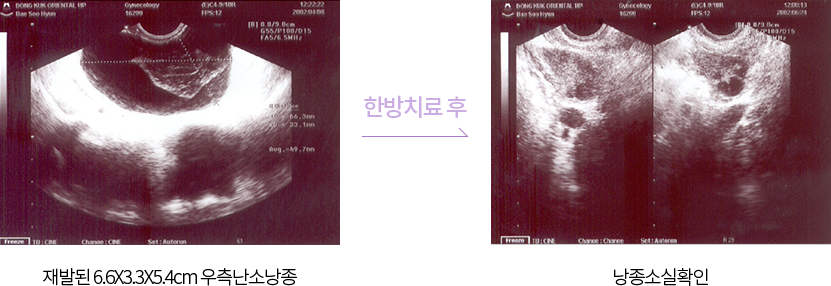

난소에 흔히 발생하는 기능성 종괴를 난소낭종이라고 합니다.

난소낭종은 악성가능성을 배제된 낭종을 치료의 대상으로 하고 있습니다.

보통 낭종 이 있으면 추적관찰을 하고 커지거나 하면 수술을 하는데요.

보다 적극적인 치료로 종괴를 줄이고. 난소의 배란기능의 회복을 돕도록 해야 합니다.

한약치료는 난소주위의 혈류순환을 촉진하고 어혈과 담음을 제거해, 낭종의 크기를 줄여줍니다.

치료사례보고